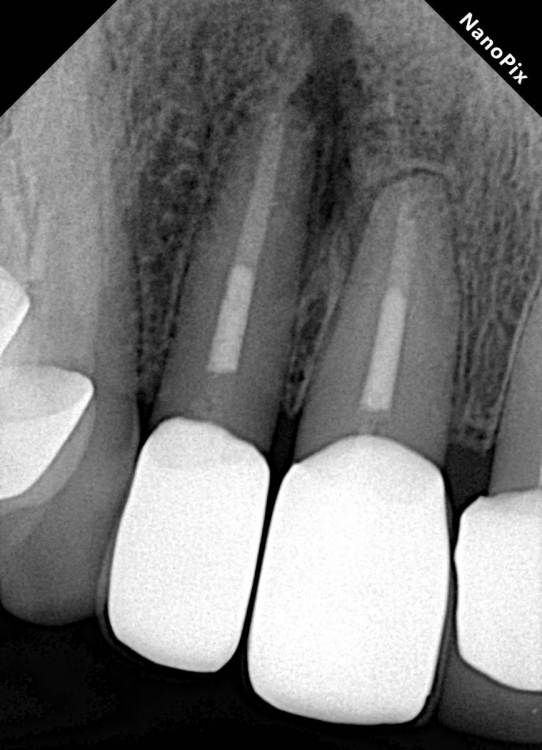

Где то через год после консервативного лечения

E8765AA6-FC49-4C36-A6D1-08B90AB26A9F.thumb.jpeg.8ff0fcf318099d06b051ce002078972c.jpeg